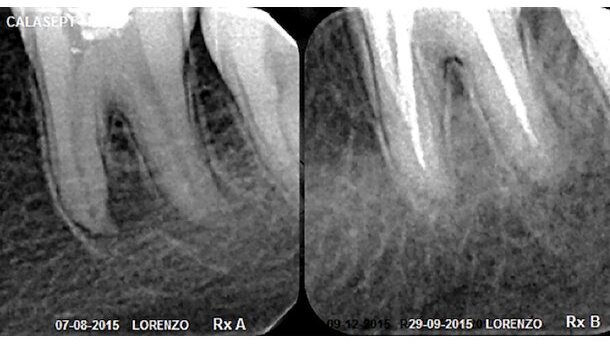

Figura 8. Radiografía RxA del recambio del biomaterial número siete, que muestra la reparación del proceso periapical y radiografía RxB ocho meses después, donde se visualiza el tratamiento finalizado. Radiografías obtenidas con Radiovisiógrafo Acteon-Satelec.

Se muestra uno de los casos clínicos resuelto favorablemente con Calasept Plus, donde se efectuó el recambio del biomaterial con una frecuencia de treinta días entre cada reemplazo (Figuras 7-9).